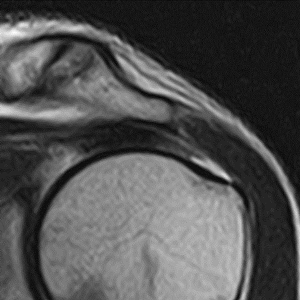

症例 2